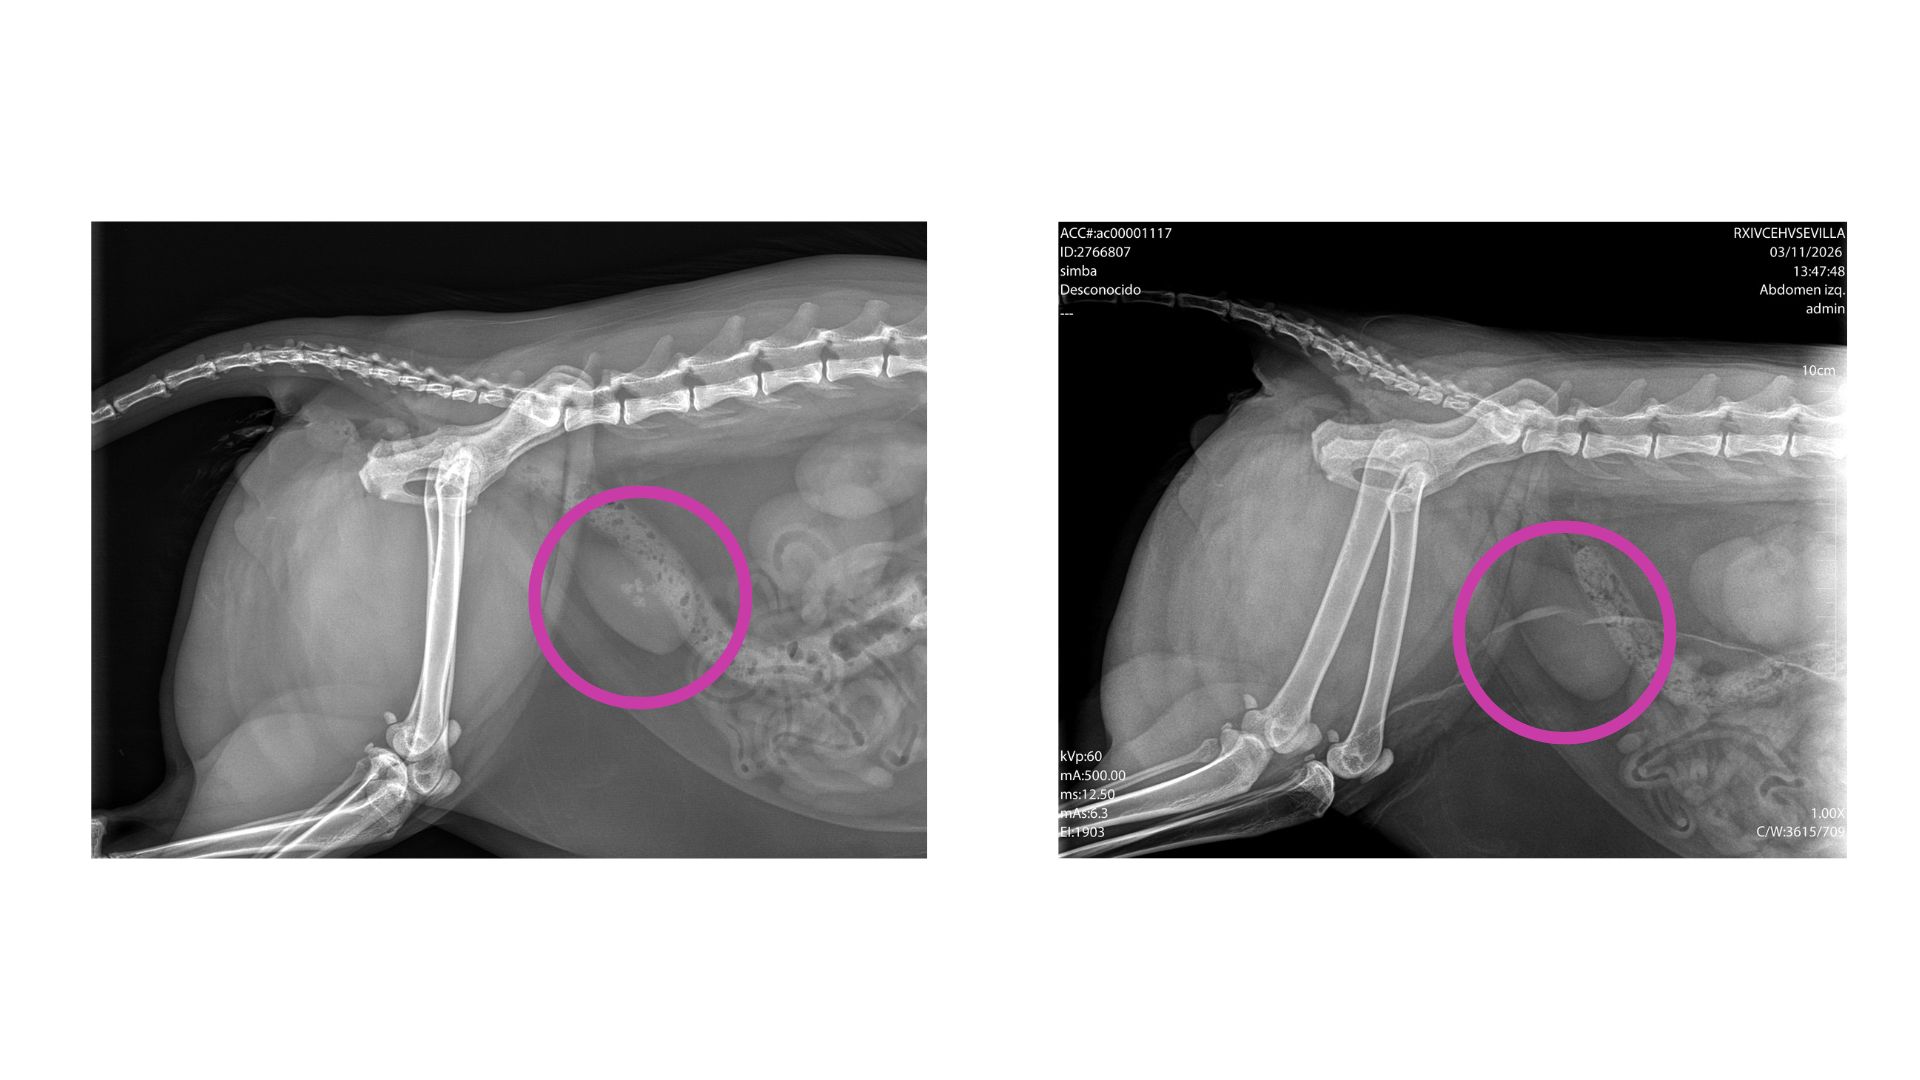

まずレントゲンを撮りました。

すると、

膀胱に石が3つある

と言われました。

エコーをしたら

石がなかった

のだそうです。

綺麗さっぱり無くなってる🤭